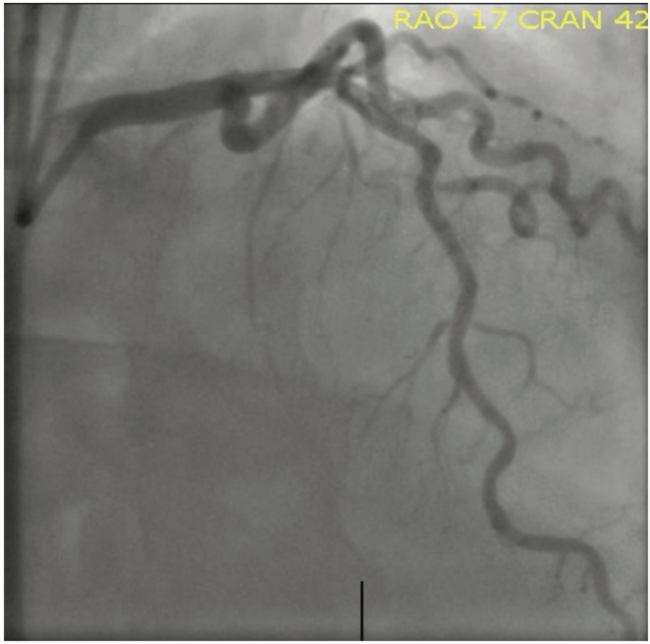

A 70-year-old gentleman initially presented for PCI after being referred for Canadian Cardiovascular Society (CCS) class 3 angina refractory to antianginal therapy (amlodipine and metoprolol succinate) after an abnormal coronary computed tomography angiography (CTA). The CTA showed a long area mid to distal LAD that was a severe stenosis with severely calcified complex plaque, with vulnerable plaque features demonstrating positive remodeling and calcium blooming, and a fractional flow reserve (FFR)CT value of <0.5 in the distal segment (Figures 1-2). His other comorbidities included hypertension and tobacco use. An initial attempt at revascularization failed after attempts to pass a 2.5 mm, 2.0 mm, and 1.5 mm Takeru PTCA Balloon Dilatation Catheter (Terumo Interventional Systems), and a Runthrough Coronary Guidewire (Terumo Interventional Systems) would not cross secondary to calcification and tortuosity (Figure 3). This index procedure was aborted and the patient was rescheduled for complex PCI. Three weeks later, he was admitted for a second attempt. A 7 Fr extra backup catheter (EBU) 3.5 guide with side holes (Medtronic) was used to engage the left main. This time, a Runthrough guidewire was advanced across the lesion into the distal LAD. Attempts at intravascular ultrasound (IVUS) (Philips) failed but did reveal a very narrow, concentrically calcified lesion in the proximal LAD. The decision to perform lesion modification was made. Next, a ViperWire was introduced; however, it would not cross the mid lesion. At this point, we chose to use the FineCross M3 Micro-Guide Coronary Catheter (Figure 4), which delivered easily and allowed us to introduce the ViperWire. Next, orbital atherectomy was performed for a total of 7 runs between 10-14 seconds from the proximal lesion through the mid lesion. The FineCross M3 Micro-Guide Coronary Catheter was then re-introduced over the ViperWire and this allowed for the exchange of a Tru-Torque guidewire (Teleflex). Next, a 3.0 mm x 12 mm IVL balloon was used to further fracture the concentric calcifications and optimize lesion prep to allow for maximal diameter stent placement (Figure 5). The proximal to mid LAD was treated with 80 bursts with 8 inflations of the IVL balloon. Angiography revealed no evidence of dissection and TIMI-III flow. Next, a 2.5 mm x 12 mm IVL balloon was used to treat the mid to distal LAD, after IVUS would not cross distal to the treated mid-portion LAD. A 6 Fr GuideLiner (Teleflex) was used to place a 2.5 mm x 24 mm Synergy stent (Boston Scientific) to the distal LAD, which was then followed in overlapping fashion with a 2.75 mm x 24 mm Synergy stent to the mid LAD (Figure 6). The proximal to mid LAD stents were further optimized with a 2.75 mm x 20 mm noncompliant (NC) balloon, inflated to 22 atmospheres for multiple inflations. Final angiography revealed no evidence of proximal or distal edge dissections, excellent stent apposition with minimal residual stenosis, and TIMI-III flow (Figure 7).